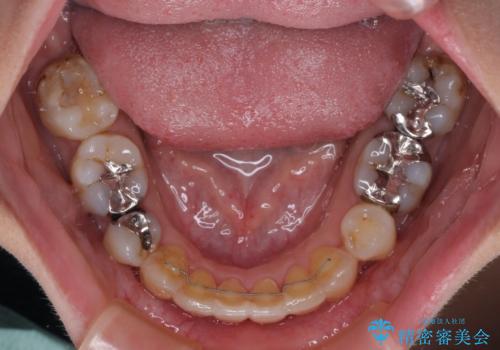

- 抜歯矯正の後戻りで前歯が突出してきていることを気にして来院された患者様です。

口元の突出感を改善するにあたり、抜歯矯正は行うことができないため、奥歯の後方移動とIPR(歯と歯の間を削る)により達成することとしました。

再度後戻りしたときに対応しやすいよう、インビザラインにて矯正治療を行うこととしました。